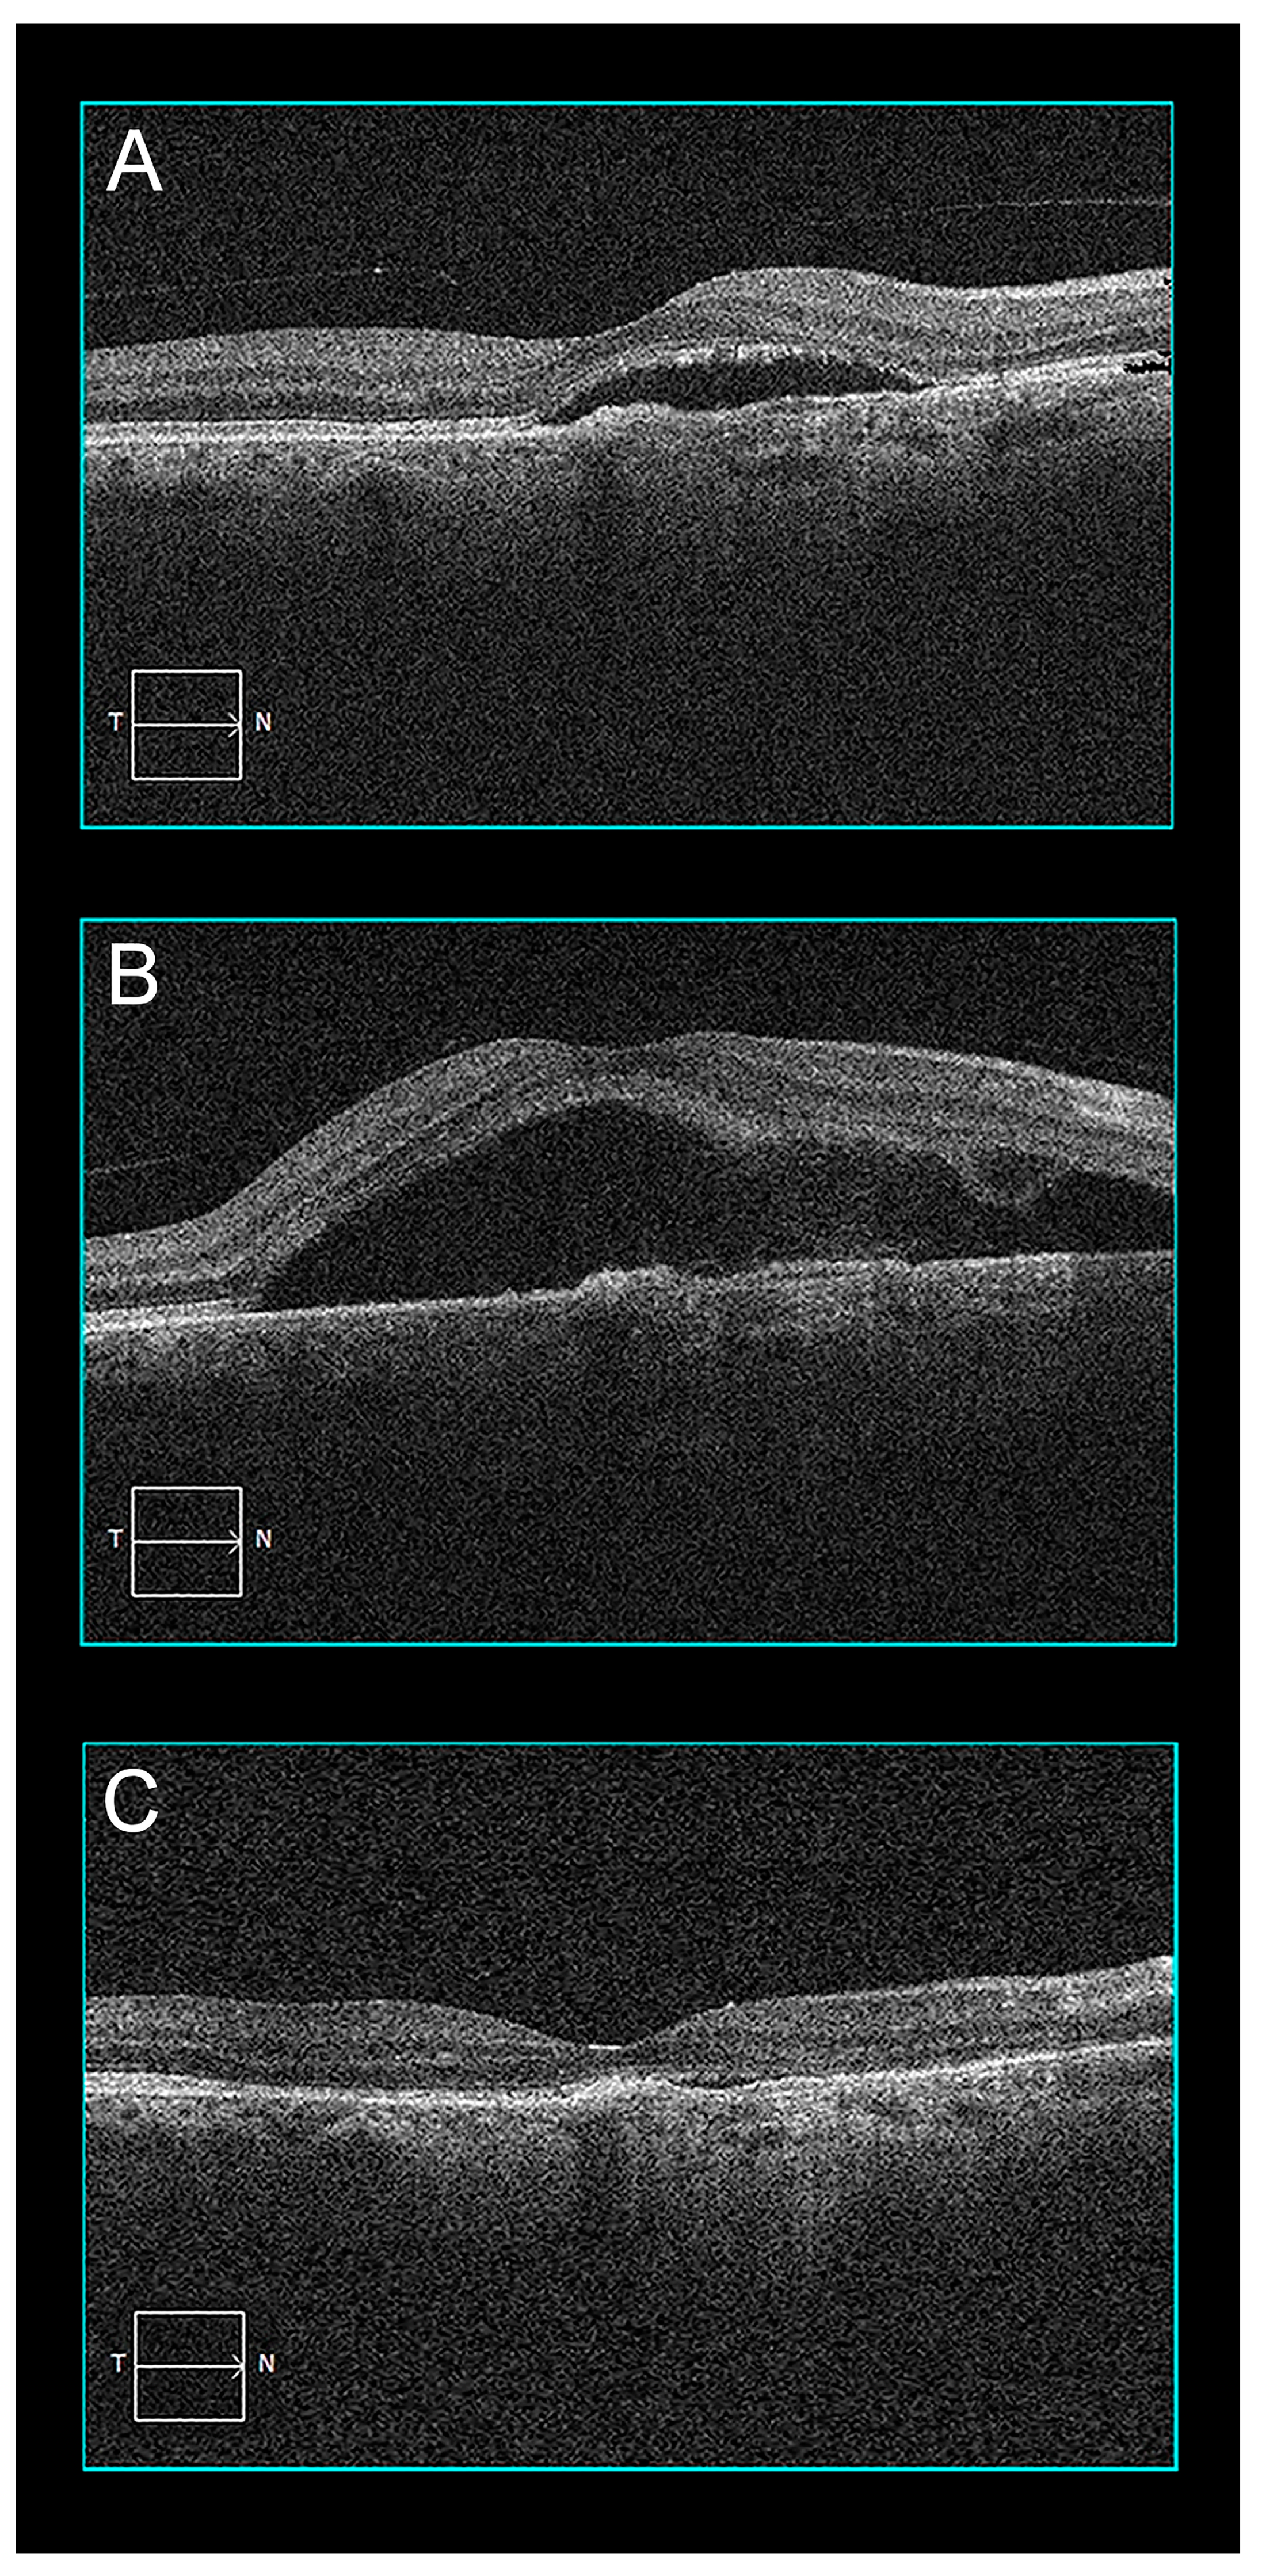

2.2. Case 2